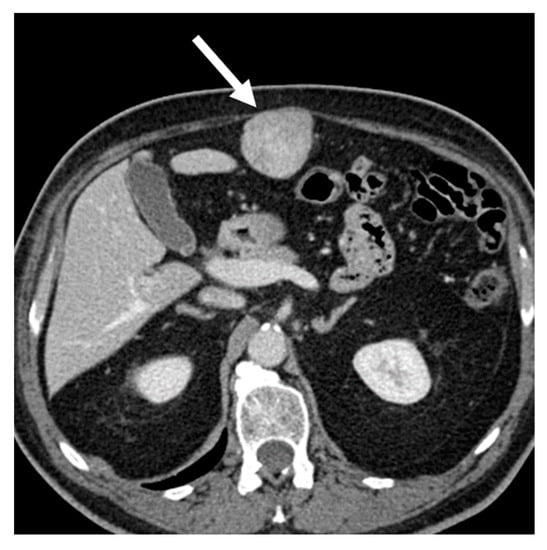

LMS is a smooth muscle tumor [38], more common than LPS in younger age groups [6]. Its most frequent location is the retroperitoneum, near the inferior vena cava [43]. LMS are heterogeneous masses (Figure 4), with irregular peripheral enhancement and enhancing solid portions, mixed with cystic, hemorrhagic, or necrotic areas. LMS show marked T2 hypointensity on MRI and are similar in attenuation to uterine myometrial smooth muscle on CT [39]. Fatty components and calcifications are usually absent [34,38]. The evidence of a large, heterogeneously enhancing, necrotic retroperitoneal mass contiguous with a vessel, with extra- and intraluminal involvement, is highly suggestive of LMS [12,37,43]. It could stem from the inferior vena cava, extending into the intrahepatic portal veins or superior mesenteric vein, or even from small vessels such as renal or gonadic veins. Differentiation from extrinsic compression can be challenging [12,40].

Figure 4.

Retroperitoneal leiomyosarcoma in a 63-year-old woman. Axial (A) and coronal (B) CT images on venous phase show a 10.2 cm heterogeneous mass with central area of low attenuation consistent with necrosis (arrow).